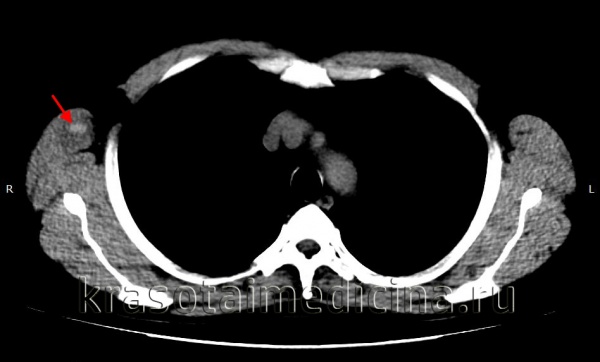

КТ ОГК показывает гиперденсное скопление крови в мышечном массиве грудной стенки справа, окруженное зоной отека.

image